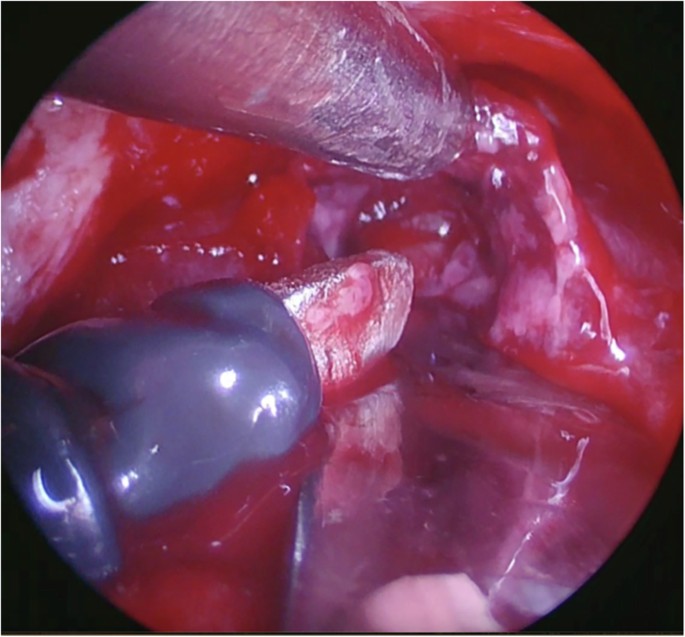

The dissector was deemed the hardest to use of the three instruments tested all approaches (Fig. 2). It performed best in the supracerebellar approach and worst in the subfrontal approach (Fig. 2). Comments included that it was “too sharp” when dissecting brain tissue, “it doesn’t return to a neutral position on its own, but it’s easy to compensate”, and that it “was good for moving tissue, but not sharp enough to cut the arachnoid tissue”. The dissector was considered easy to use for manipulating arachnoid tissue (albeit not sharp enough), blood vessels, and brain tissue, in the first animal. In the second, the usability of the dissector was considered very easy for manipulating arachnoid tissue and blood vessels (very appropriate and precise); however, the dissector was difficult to use in the manipulation of brain tissue, requiring adaptation according to tissue fragility. Its use in vivo is demonstrated in Fig. 3.